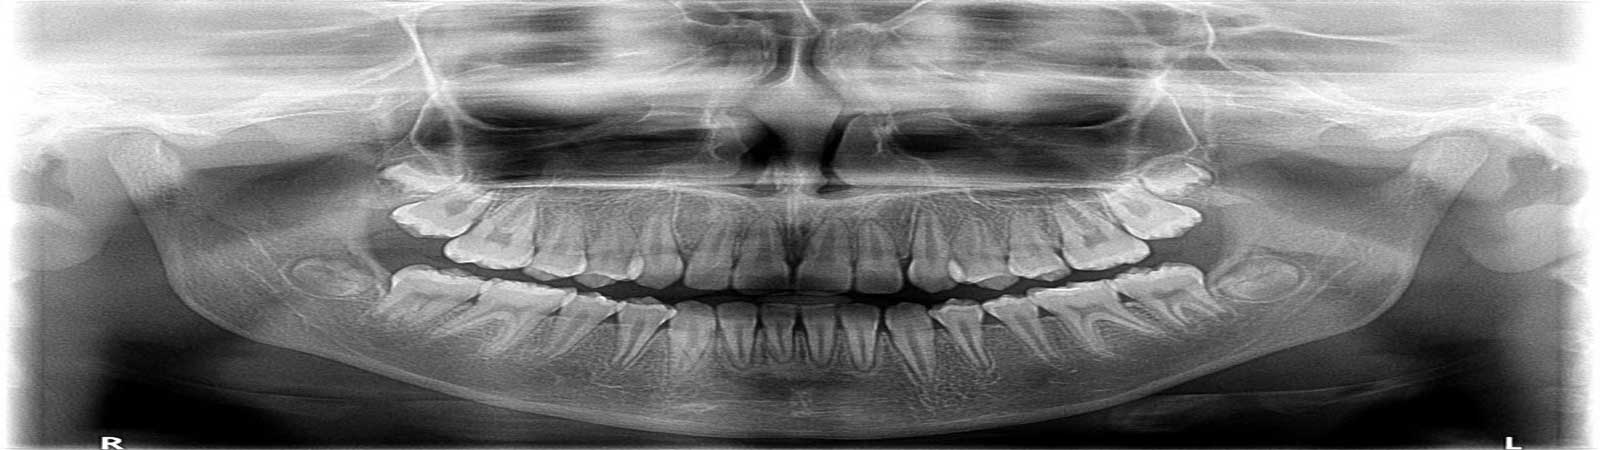

رادیوویزیوگرافی دیجیتال (RVG) جدیدترین فناوری پرتوی ایکس در دندانپزشکی است. رادیوویزیوگرافی دیجیتال مجهز به نرم افزار آنالیز تصویری ویژه ای است که در آن این امکان فراهم شده است که تصاویر بزرگ شده و آنالیز شود و در پرونده بیمار ذخیره گردد. برخی از مزایای رادیوویزیوگرافی دیجیتال عبارتند از:

- کاهش 80 درصدی تشعشع بیمار در مقایسه با تصاویر پرتوی ایکس سابق

- تصویر برداری سریعتر بدون فیلم پرتوی ایکس و تولید تصاویر

- کیفیت بالای تصاویر دیجیتال که میتوان آن را آنالیز و پردازش کرد